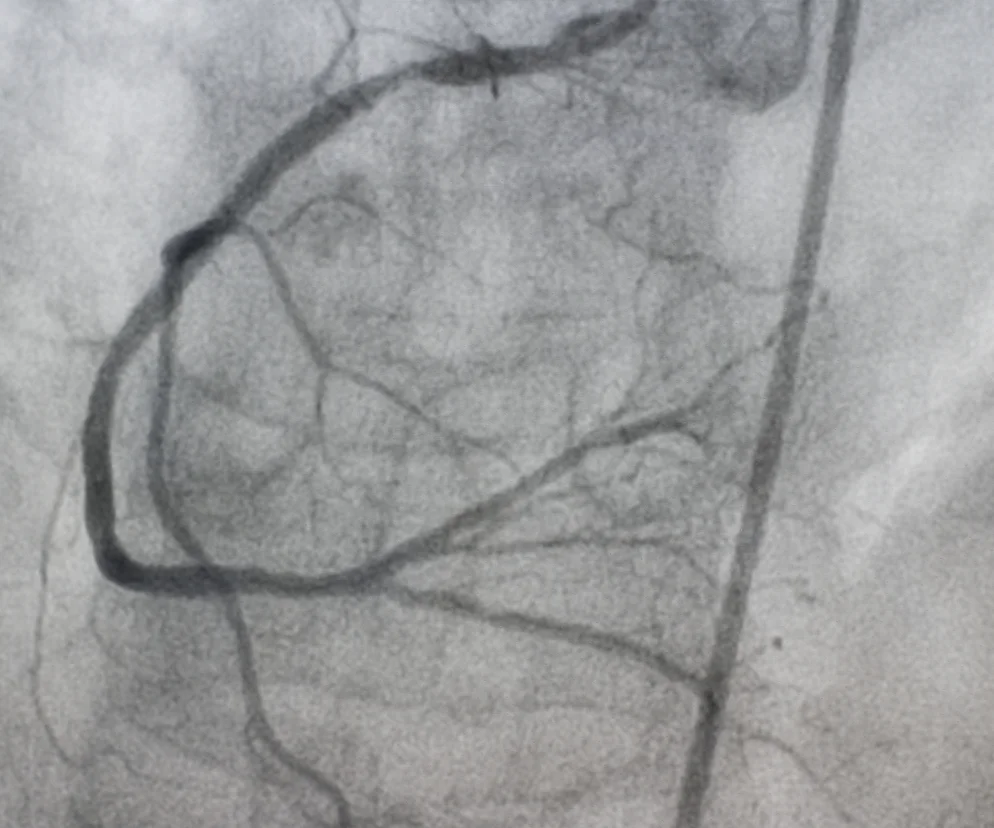

Arteriografia to badanie radiologiczne (RTG z użyciem kontrastu) polegające na obrazowaniu tętnic (np. aorty, tętnic nerkowych, tętnic mózgu) niewidocznych na zwykłym zdjęciu rentgenowskim. Jak przebiega badanie? Czy do arteriografii trzeba się specjalnie przygotować?

Arteriografia to inwazyjne badanie tętnic, które wykonuje się w szpitalu. Zazwyczaj kieruje się na nią osoby, u których trzeba podjąć decyzję o ewentualnym leczeniu operacyjnym. Najczęściej wykonuje się:

• arteriografię tętnic wieńcowych.

Zostaniesz poproszona o położenie się na plecach na specjalnym ruchomym stole. Lekarz wstrzyknie ci podskórnie znieczulenie miejscowe w okolicy nakłuwanego naczynia. Potem nakłuje to naczynie igłą i przez nią wprowadzi do jego światła tzw. prowadnik (wąski giętki pręcik o średnicy kilku milimetrów) i cewnik. Przez cewnik wleje kontrast, a następnie wykona serię zdjęć RTG (zwykle około 20). Jeśli zajdzie taka konieczność, przez cewnik może również podać ci leki, poszerzyć naczynie bądź je zamknąć przez wytworzenie "czopów" (tzw. embolizacja).